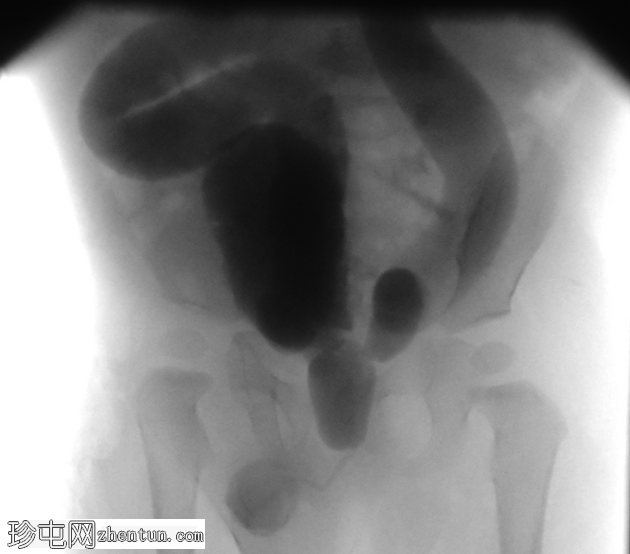

后尿道可见线状透亮区,近端尿道扩张,膀胱颈肥厚,膀胱壁小梁化,双侧输尿管膀胱反流程度较高(表现为输尿管扩张和迂曲)。

左侧输尿管异位开口于膀胱颈下方的后尿道。

这是一个典型的后尿道瓣膜病例,其特征为膀胱出口慢性梗阻。

左侧输尿管异位插入尿道。